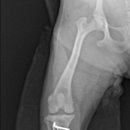

• 24시 에피소드 동물 메디컬 센터 | 만촌동 동물병원 강아지 요골·척골 골절 수술 후기 [24시에피소드동물메디컬센터]

만촌동 동물병원 강아지 요골·척골 골절 수술 후기 [24시에피소드동물메디컬센터] 만촌동 동물병원 ​ 안녕하세요. ​ 풍부한 경험과 따듯한 진료를 바탕으로, 반려동물의 건강하고 행복한 하루하루를 함께 만들어 가는 만촌동 동물병원 24시에피소드동물메디컬센터 입니다. 24시에피소드동물메디컬센터 대구광역시 동구...

에피소드동물메디컬센터(2025-06-26 12:41:00)